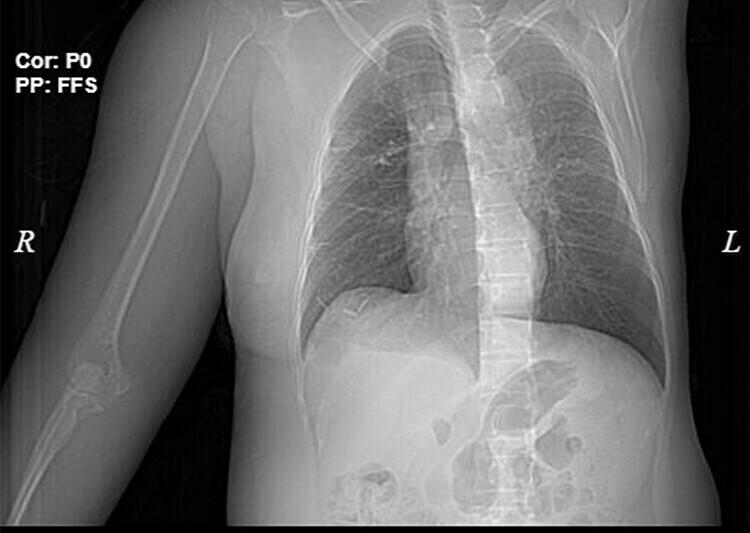

Các bác sĩ chẩn đoán bệnh nhân ung thư vú giai đoạn cuối di căn hạch nách và xương cánh tay phải. Vùng da đắp thuốc nam bị nhiễm trùng có nguy cơ hoại tử, nhiễm khuẩn huyết.

Bác sĩ Hứa Văn Đức Trưởng khoa Ung bướu, nhận định bệnh nhân đến viện giai đoạn muộn, u không còn khả năng phẫu thuật. Cách điều trị là dùng kháng sinh kiểm soát tình trạng nhiễm trùng, kiểm soát đau, điều trị hóa chất theo chu kỳ.